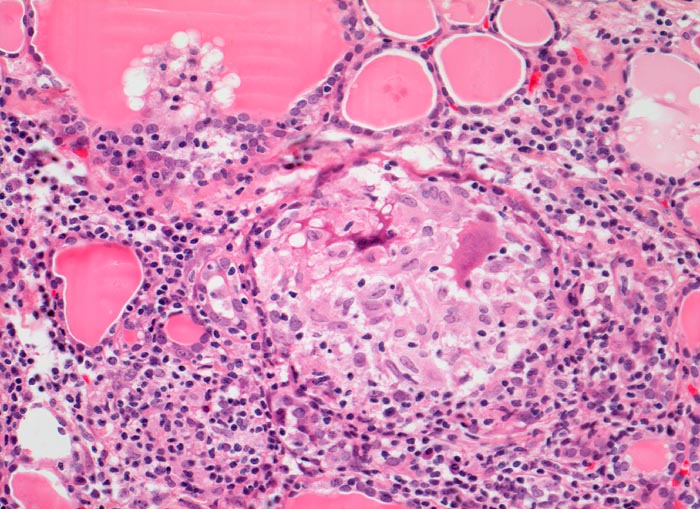

AP/ Subakute Thyeroiditis de Quervain

Subakute Thyeroiditis de Quervain

Schilddrüse